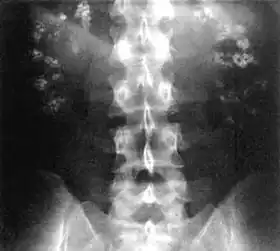

Bilateral nephrocalcinosis seen on an abdominal x-ray | |

Nephrocalcinosis, once known as Albright's calcinosis after Fuller Albright, is a term originally used to describe the deposition of poorly soluble calcium salts in the renal parenchyma due to hyperparathyroidism. The term nephrocalcinosis is used to describe the deposition of both calcium oxalate and calcium phosphate.[1] It may cause acute kidney injury. It is now more commonly used to describe diffuse, fine, renal parenchymal calcification in radiology.[2] It is caused by multiple different conditions and is determined by progressive kidney dysfunction. These outlines eventually come together to form a dense mass.[3] During its early stages, nephrocalcinosis is visible on x-ray, and appears as a fine granular mottling over the renal outlines. It is most commonly seen as an incidental finding with medullary sponge kidney on an abdominal x-ray. It may be severe enough to cause (as well as be caused by) renal tubular acidosis or even end stage kidney disease, due to disruption of the kidney tissue by the deposited calcium salts.